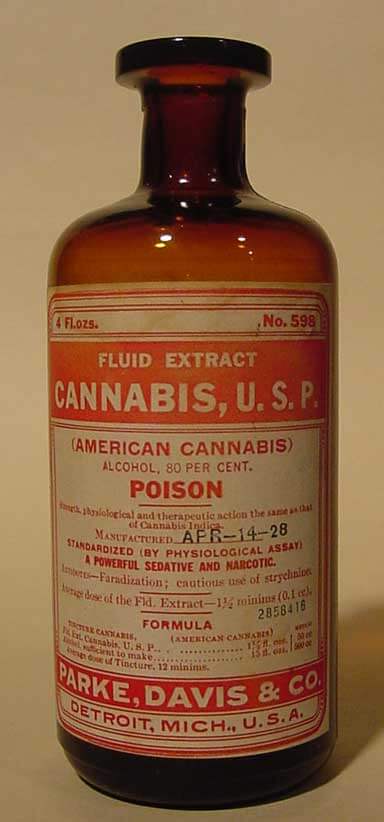

The Original 1899 Merck Manual: Natural, Food-Based Medical Treatments

www.connersclinic.com

www.connersclinic.com

manual merck 1899 cannabis natural treatments medical based medicine